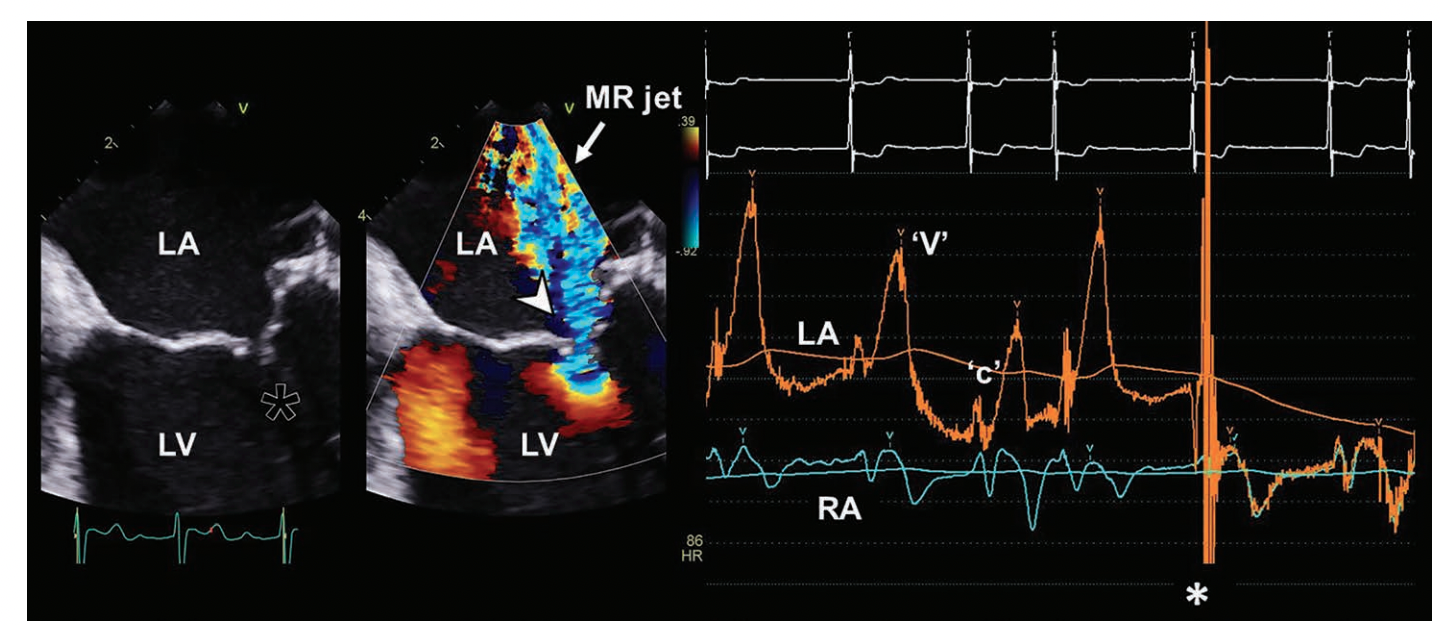

On physical exam, MR is usually detected by loud, holosystolic murmur and by transthoracic or transesophageal echocardiography3 (Figure 4), where a large, eccentric MR high velocity jet (arrow) into the LA can be visualized. Hemodynamically, severe MR is often associated with large ‘v’ waves (Figure 4, right side). Note on this tracing that there is a ‘c’ wave, but no ‘a’ wave, as the patient is in atrial fibrillation. The simultaneous right atrial pressure (RA) has no significant ‘v’ wave, indicating little if any tricuspid regurgitation or very high RA chamber compliance. The pullback of the LA pressure catheter across the atrial septum at the vertical line (*) showed matching of LA/RA pressures.